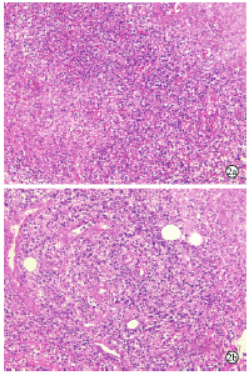

一例奥妥珠单抗+苯达莫司汀方案治疗腮腺原发黏膜相关淋巴组织淋巴瘤患者4个周期后获得完全缓解

病史摘要:69岁女性,主诉发现右侧耳前区肿物5月余。起初肿物“黄豆样”大小,后逐渐增大。于当地医院X线检查后转至上级医院,后就诊于我院口腔外科。诊疗过程:完善右侧腮腺区CT平扫 + 增强等检查后入院行手术,术后病理提示“MALT淋巴瘤”。血常规、PET - CT、骨髓检查等进一步明确病情,诊断为MALT淋巴瘤,Ⅱ期A组,IPI评分1分,低危组。采用奥妥珠单抗联合苯达莫司汀治疗4个周